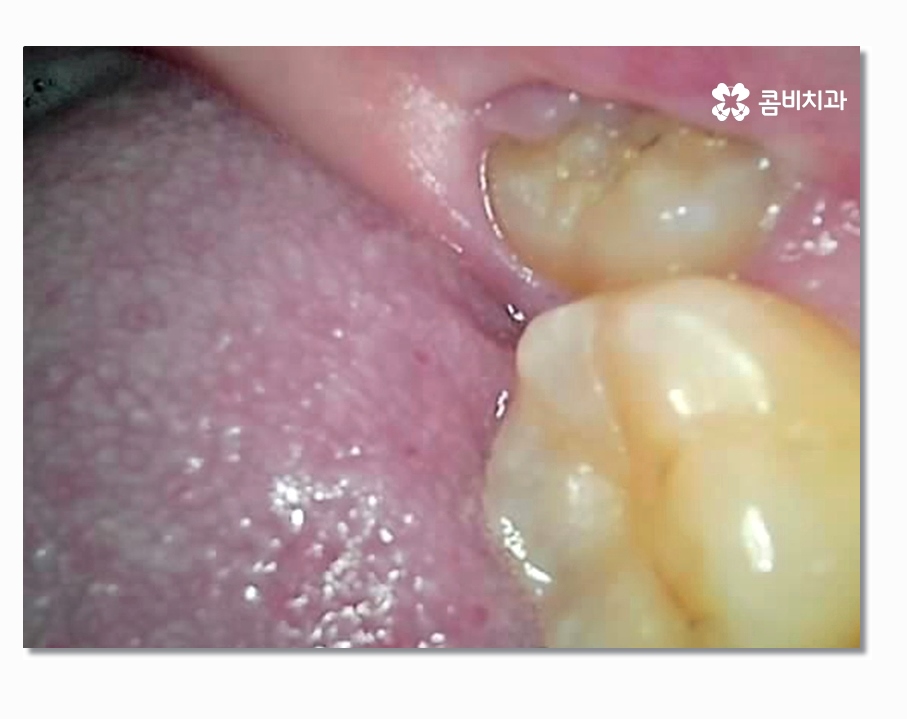

보시는 것처럼 부분매복사랑니의 경우 음식물이 끼기 쉽고

치석이 쌓이기 쉽지만 칫솔질은 어렵기 때문에

충치가 발생하여 어금니까지 함께 손상되거나

특히 잇몸질환이 발생하는 경우가 많다고 할 수 있는데요

사랑니 주변 잇몸 상태가 악화되어 치주염으로 이어지는 경우가

상당히 많은데 기본적으로는 양치가 잘되지 않아서 쌓인 치석으로 인해

치주질환에 시달리는 경우도 많지만 부분매복사랑니 처럼

치아의 상태로 인해서 염증이나 잇몸질환에 시달리는 경우도 있으므로

문제가 심해지기 전에 발치를 고려해야 할 수 있어요.